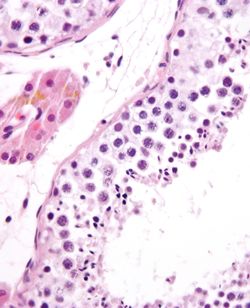

![]() أنيبيب ناقل للمني ويظهر حيوان منوي ناضج. صبغة H&E. | |

يحدث تكون النطاف في عدّة بنى في الجهاز التكاثريّ الذكريّ. إذ تحدث المراحل الأولى داخل الخصى وتتقدّم مراحل هذه العمليّة في البربخ، حيث تُخزَّن الأعراس حتى لحظة القذف. إذاً فالنُبيبات الناقلة للمني في الخصيّة هي نقطة الانطلاق لهذه العمليّة، إذ تبدأ الخلايا الجذعيّة بزرة النطاف المجاورة لجدار النبيبات الداخليّ بالانقسام باتجاه مركزيّ، إذ تبدأ من الجدران وتتجّه نحو اللمعة لتنتج نطافاً غير ناضجة.[3] بينما يحدث النضج في البربخ. يرتبط نجاح عمليّة تكون النطاف بموقع حدوث العمليّة [الخصيتان/كيس الصفن] بشدّة، إذ تتطلَّب هذه العمليّة درجة حرارة أخفض من درجة حرارة الجسم كي تكون النطاف الناتجة قادرة على الحياة، وتحديداً أخفض من درجة حرارة الجسم بدرجة إلى ثمان درجات مئويّة من حرارة الجسم الطبيعيّة (و التي تبلغ 37 درجة مئويّة).[6] سريرياً، لا تؤدي التقلُّبات الصغيرة في درجة الحرارة ، كتلك الناتجة عن ارتداء حزام الدعم الرياضيّ إلى ضرر في عدد أو حيويّة النطاف.[7]